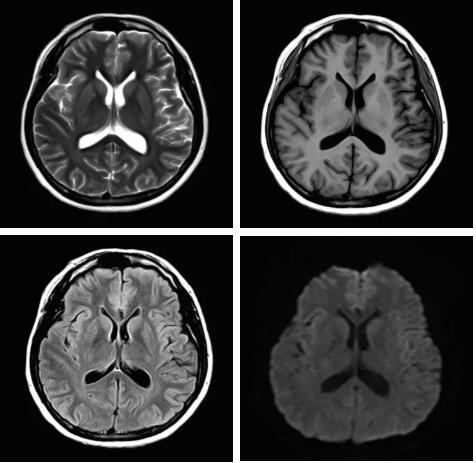

見所未見 微小腫瘤無處遁藏——

“螢火蟲”成像技術(shù) 顱內(nèi)腫瘤微小病灶檢出新發(fā)現(xiàn)

此技術(shù)主要用于神經(jīng)系統(tǒng)惡性腫瘤,以及其他腫瘤腦轉(zhuǎn)移瘤篩查。傳統(tǒng)情況下做腫瘤腦轉(zhuǎn)移篩查,很容易漏掉5mm以下小病灶,臨床發(fā)現(xiàn)后干預(yù)治療比較晚,要實現(xiàn)2mm高空間分辨率和超薄層全腦掃描在保證信噪比的情況下需要很長時間大概十多分鐘,而且薄層增強(qiáng)序列顱內(nèi)血管呈高亮信號,會干擾顱內(nèi)小病灶的觀察,血管和小病灶區(qū)分困難。佳能”螢火蟲”成像技術(shù)既可以實現(xiàn)高空間分辨率和超薄層(最薄可實現(xiàn)0.2mm)全腦掃描,掃描時間短,2-3分鐘即可實現(xiàn)全腦3D掃描,同時避免了血管高亮信號的干擾,對顱內(nèi)原發(fā)或繼發(fā)的微小腫瘤檢查有重大意義。“螢火蟲”成像技術(shù)具有磁敏感效應(yīng),對于亞急性血敏感敏感,可以區(qū)分出血和強(qiáng)化的腫瘤。